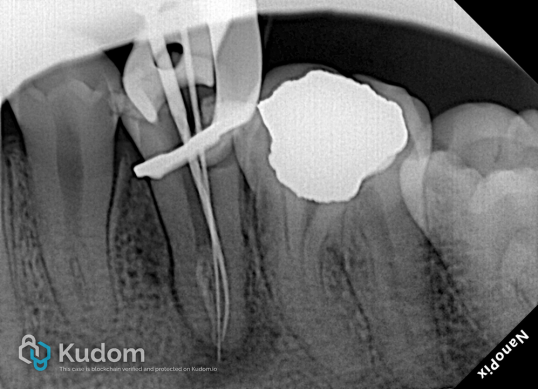

Radiographic Examination:Pre-operative radiographs revealed extreme anatomical complexity—a mandibular second premolar with 4 distinct canals and an apical split.

Isolation and Access:Rubber dam isolation was strictly established. The old filling material was removed with proper access opening, followed by meticulous scouting of the missed canals.

Retreatment and Shaping:

The old gutta-percha was effectively heated and removed using the “Elite fill-p”system. Canal shaping was masterfully executed using the EZ Shaper Pro rotary file sequence (Ezx, Ez1, Ez2, Ez3, Ez4, Ez5).

Irrigation & Obturation:A comprehensive irrigation protocol was performed. The complex root canal system was three-dimensionally sealed using the modified warm vertical compaction technique.